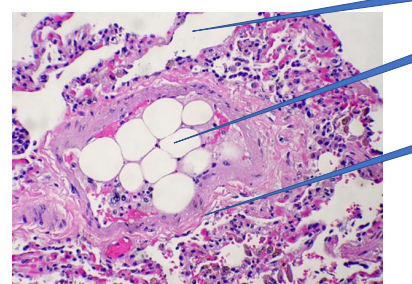

Pulmonary fat embolism

1- normal alveoli

2- fat emboli

3- vessel wall